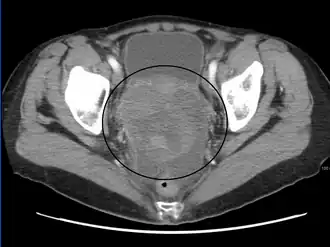

CT scanning is preferred to assess the extent of the tumor in the abdominopelvic cavity, though magnetic resonance imaging can also be used.[28] CT scanning can also be useful for finding omental caking or differentiating fluid from solid tumor in the abdomen, especially in low malignant potential tumors. However, it may not detect smaller tumors. Sometimes, a chest x-ray is used to detect metastases in the chest or pleural effusion. Another test for metastatic disease, though it is infrequently used, is a barium enema, which can show if the rectosigmoid colon is involved in the disease. Positron emission tomography, bone scans, and paracentesis are of limited use; in fact, paracentesis can cause metastases to form at the needle insertion site and may not provide useful results.[29] However, paracentesis can be used in cases where there is no pelvic mass and ascites is still present.[29] A physician suspecting ovarian cancer may also perform mammography or an endometrial biopsy (in the case of abnormal bleeding) to assess the possibility of breast malignancies and endometrial malignancy, respectively. Vaginal ultrasonography is often the first-line imaging study performed when an adnexal mass is found. Several characteristics of an adnexal mass indicate ovarian malignancy; they usually are solid, irregular, multilocular, and/or large; and they typically have papillary features, central vessels, and/or irregular internal septations.[31] However, SCST has no definitive characteristics on radiographic study.[32]